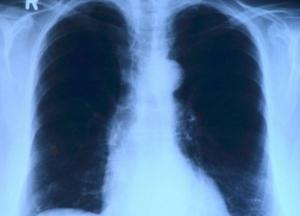

Медики назвали ранний признак рака легких

Рак легких является одним из самых распространенных видов онкологических заболеваний. Его риск резко возрастает при возникновении у человека зудящей и болезненной сыпи, передает FaceNews.ua.

Болезнь может распространиться на другие части тела, что может привести к летальному исходу. Поэтому важно обнаруживать ранние и необычные признаки, предупреждающие о риске онкологии. Медики предупредили, что сыпь может сигнализировать о развитии у человека рака легких.

Специалисты уточняют, что такая сыпь пурпурного цвета – часть необычного воспалительного заболевания, называемого дерматомиозитом, она обычно появляется на веках или на лице в целом.

Кроме того, у пациентов может возникать прогрессирующая мышечная слабость в области бедер, рук и плеч, при раке легких.

«Дерматомиозит у взрослых связан с повышенной вероятностью развития рака, особенно шейки матки, легких, поджелудочной железы, груди, яичников и желудочно-кишечного тракта», – предупредили эксперты из клиники Майо.